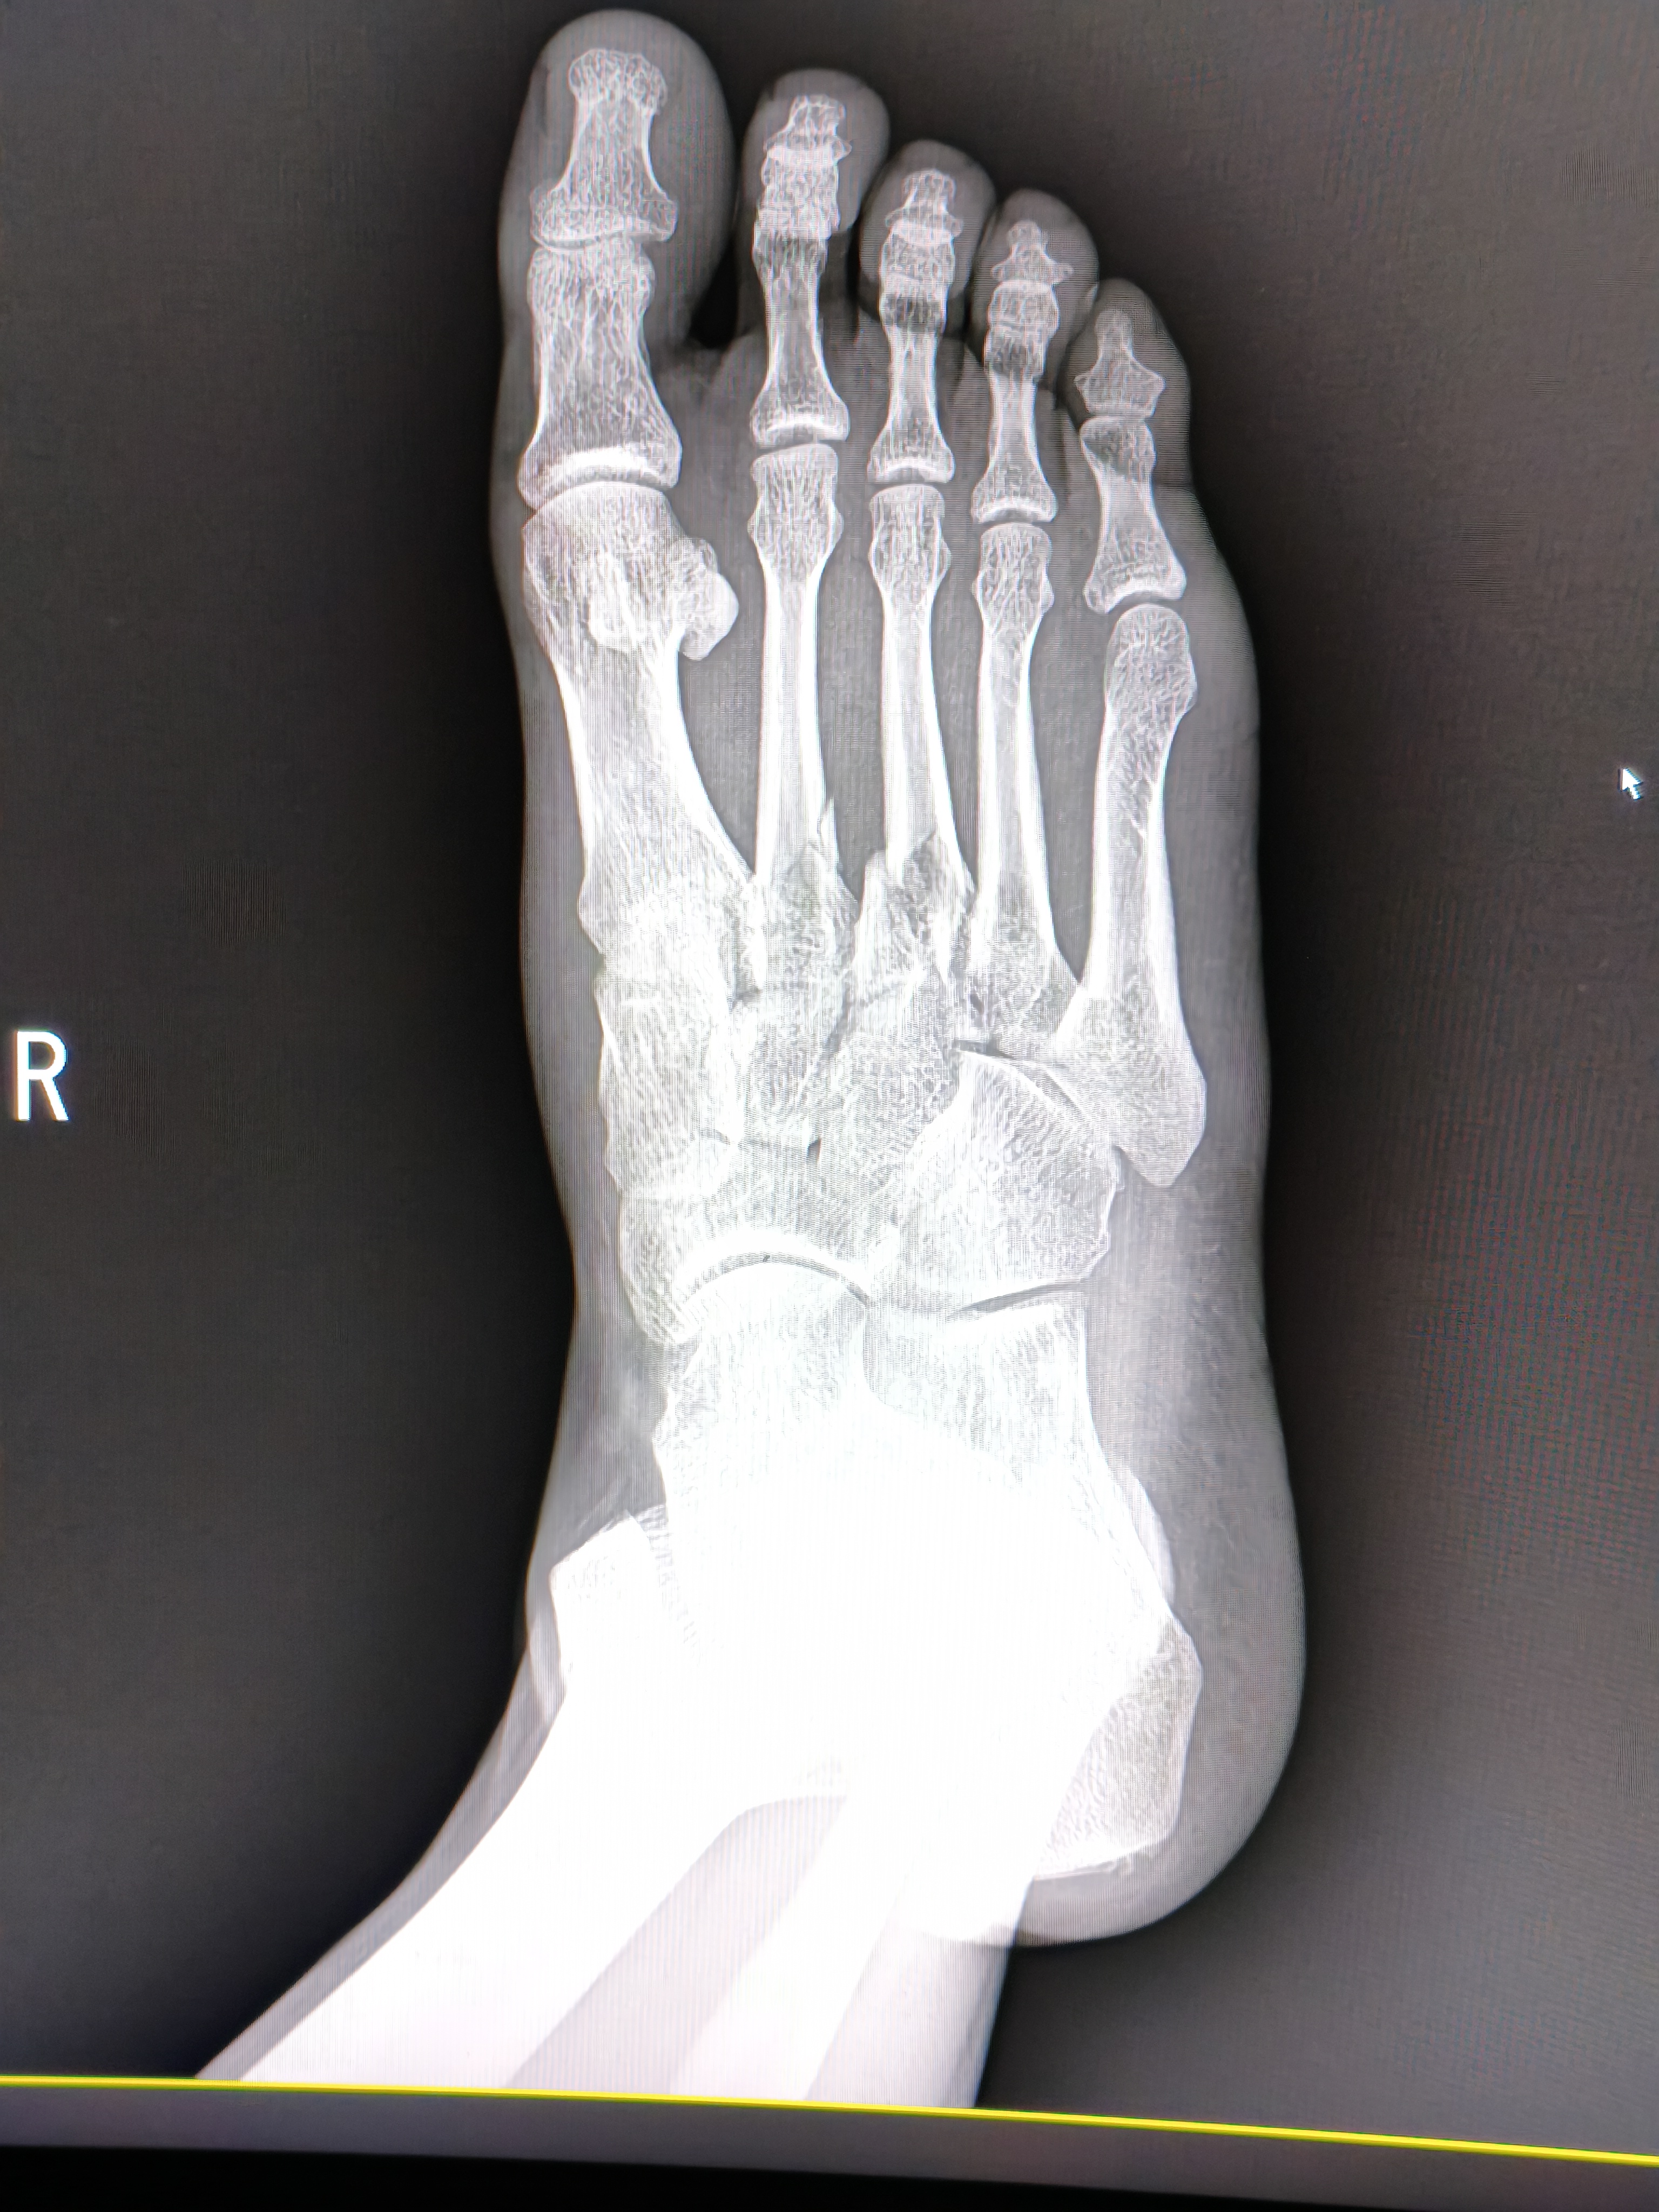

지난주 토요일 발등 골절 판정을 받아 두군데 진료받았는데 병원비가 너무 비싸서 수술을 미뤄도 될 상황인지 알고 싶습니다.

예후가 안좋은 부위라는데 수술비로 다 나가면 생활이 안되어서요.

실손보험들어놓으신것있으면 좋을텐데 걱정되는군요, 수술하시는게 맞습니다 아니면 평생 신경쓰이게 불편할가능성이 높거든요

발등 골절은 방치 시 보행 장애 등 후유증이 크므로,

긴급복지지원이나 재난적 의료비 제도를 통해 비용 부담을 줄여서라도

골든타임 내 수술받으시는 것이 나중을 위해 훨씬 안전합니다.